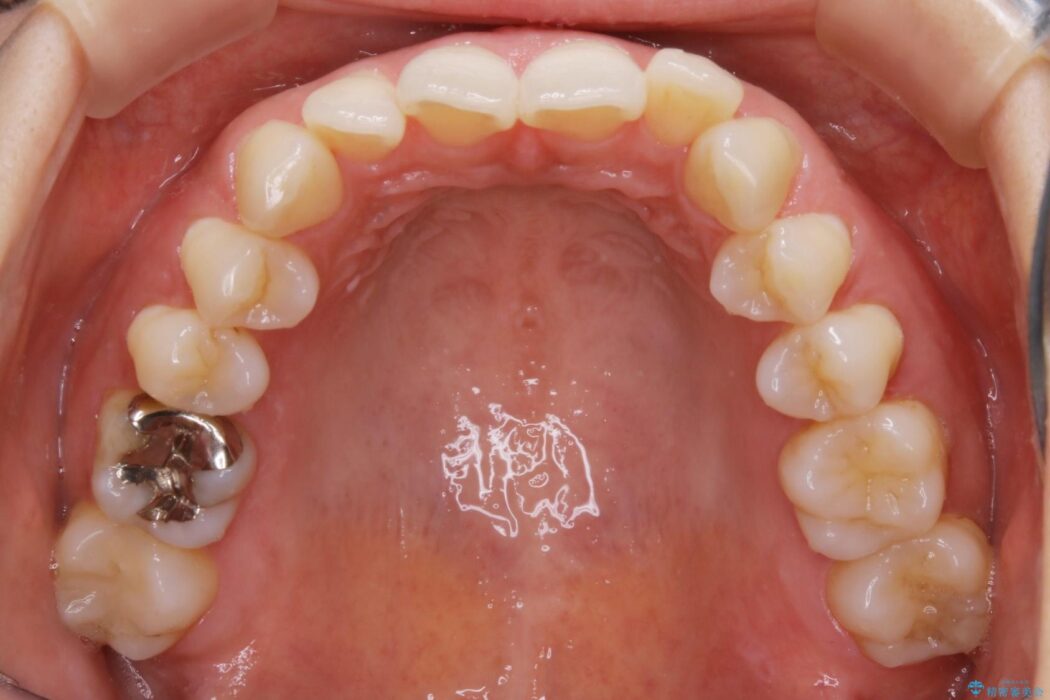

検査したところ歯の叢生自体は歯列幅の拡大やディスキング(IPR)で解決できる範囲内でした。

ですが、上顎左側の歯が前方へ寄っている状態であるため噛み合わせにズレが生じていました。

よって噛み合わせのズレをマイクロインプラントを使用して歯を移動させ、インビザラインにて歯列の整えを行うこととしました。